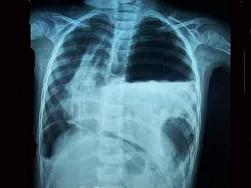

问题 2岁肺炎患儿突然烦躁不安,呼吸困难,面色青紫。心率160次/min,左侧肺部叩诊鼓音,听诊呼吸音减低。纵隔向右移位。肝右肋下2.5cm,胸片见图。该患儿最可能合并 ( )

选项 A、肺不张 B、支气管异物 C、心力衰竭 D、脓气胸 E、脓胸

答案 D